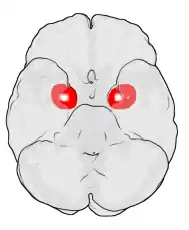

Amygdala

Die Amygdala oder der Mandelkern ist ein paariges Kerngebiet des Gehirns im zur Mitte gelegenen Teil des jeweiligen Temporallappens. Sie ist Teil des limbischen Systems. Der Name der Amygdala (fachsprachlicher Plural: Amygdalae) ist nach ihrem Aussehen aus lateinisch amygdala, dies aus altgriechisch ἀμυγδάλη ‚Mandel(kern)‘, geschöpft. Sie wird auch als Corpus amygdaloideum bezeichnet.

Man unterscheidet am Mandelkernkomplex drei unterschiedliche Gebiete: Zum einen die zentromediale Kerngruppe, unter anderem mit den Nuclei centralis und medialis – beides Abkömmlinge des Striatums. Dann der basolaterale Komplex, wobei hier die Kerne Nucleus lateralis, Nucleus basalis – der sich zusätzlich in einen kleinzelligen innenliegenden und einen großzelligen seitlichen Teil aufspaltet – und Nucleus basolateralis zu nennen wären. Und als drittes die kortikale Kerngruppe mit dem Nucleus corticalis.